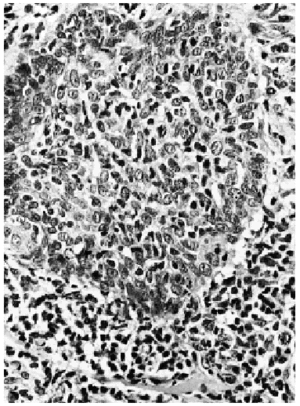

Una biopsia tomada de una de las placas de alopecia mostraba en dermis reticular un denso infiltrado linfoide atípico con células cerebriformes dispuestas exclusivamente alrededor de folículos pilosos, con permeación folicular (figs. 2, 3 y 4). En estas estructuras se advertían pequeños microabscesos, así como células atípicas aisladas con halos perinucleares. No existía mucinosis folicular y la epidermis suprayacente no mostraba epidermotropismo. El estudio inmunohistoquímico fue intensamente positivo para CD3, CD43 y negativo para CD79 alfa y CD20. Una biopsia de la adenopatía inguinal demostró infiltración ganglionar específica por linfoma cutáneo.

Fig. 4.--Imagen a gran aumento con los linfocitos atípicos distribuidos alrededor de restos de folículo, con intensa permeación del mismo (hematoxilina-eosina).